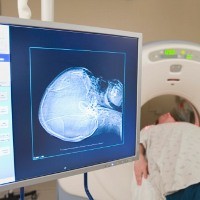

Kanker otak merupakan tumor ganas yang tumbuh di sel otak, baik berasal dari sel otak sendiri (primary brain cancer) maupun dari organ lain yang menyebar ke otak (secondary atau metastatic brain cancer). Beberapa jenis kanker otak yang dikenal antara lain glioma, meningioma, pituitary adenoma, vestibular schwannoma, dan medulloblastoma.

Operasi dilakukan untuk kanker yang bisa dijangkau lewat pembedahan dan tidak berada di dekat bagian otak yang sensitif. Risiko pembedahan pada kanker otak cukup tinggi, mulai dari kerusakan saraf yang bisa memicu gangguan panca indra serta perdarahan di otak yang bisa memicu infeksi.